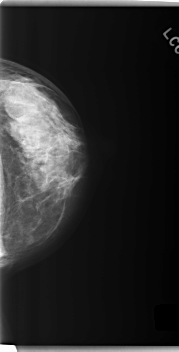

C_0279_1.LEFT_CC

LEFT_CC LINES 5968 PIXELS_PER_LINE 3032 BITS_PER_PIXEL 12 RESOLUTION 50 NON_OVERLAY